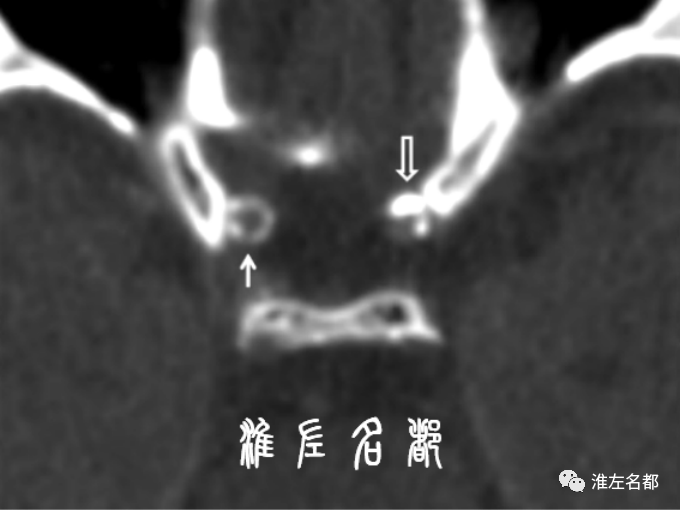

对于一些管径相对粗大的颈部血管,颈部CTA原始图在管腔含碘高密度血液的衬托下,可显示一些明显的血管壁病变,如斑块组织、夹层壁内血肿和动脉炎性管壁增厚。但是,由于CT技术是基于物质原子序数和/或密度差异来形成对比度,一般只能识别显著高密度的斑块钙化,以及明显低密度的斑块脂质成分,而对于其他构成成分相近的软组织辨别能力差。对于颅内动脉病变,除了高密度管壁钙化外,就很难获取其他的颅内动脉管壁病变信息了。

有别于颈部血管疾病,在常规血管影像学上,不同病因颅内动脉狭窄-闭塞的病变位置和管腔形态改变方面,往往缺乏特征性,给病因诊断和鉴别诊断带来很大困惑。与此同时,因颅内动脉管壁菲薄,尺寸细小,并位于颅骨腔深部,常规的MRI或超声技术极难清晰显示颅内动脉的管壁异常改变,CT也仅限于显示颅内动脉管壁高密度钙化。并且,已常规应用于冠脉疾病的血管内超声和OCT技术也不适合作为评估颅内动脉病变的常规方法,具体理由详见前文。